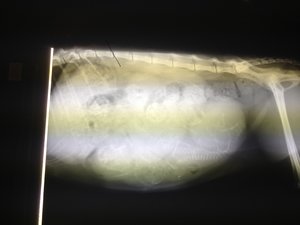

so hier die bilder

Anhänge

• 003.JPG

003.JPG

1,9 MB · Aufrufe: 15

• 013.JPG

013.JPG

1,7 MB · Aufrufe: 28

• 012.JPG

012.JPG

1,5 MB · Aufrufe: 21